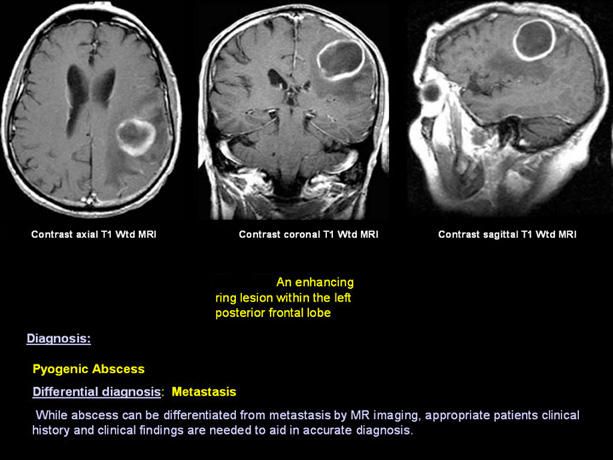

Infections

Metastatic